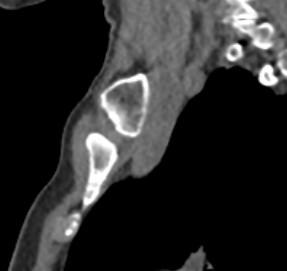

Однако классический рентген не всегда обеспечивает качественную визуализацию ГКС из-за наложения друг на друга изображений костных структур. Компьютерная томография лишена таких недостатков. При проведении КТ излучатель рентгеновских лучей совершает круговые движения вокруг исследуемой области, проводя сканирование в различных плоскостях. В результате получаются детальные снимки высокого качества, а после цифровой обработки – трехмерные модели грудино-ключичных сочленений в мельчайших подробностях.

КТ благодаря быстроте, доступности и высокой информативности часто назначается в экстренных ситуациях, например, при травмах и в случае необходимости проведения оперативного лечения. Поэтому метод особенно востребован в ортопедии и травматологии. На снимках КТ и трехмерных изображениях можно оценить состояние суставных поверхностей грудино-ключичных сочленений, а в случае перелома определить точную локализацию костных отломков.